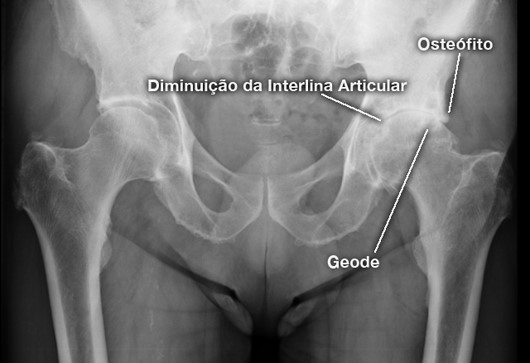

Na artrose da anca existe um desgaste da cartilagem articular originando dor marcada, limitação da mobilidade articular e diminuição da capacidade de marcha.

Existem alguns factores de risco para a coxartrose com sejam a existência de um história familiar da doença, a obesidade, lesões da cartilagem articular ou alterações da morfologia da anca, como sejam a displasia e o conflito femoro-acetabular. Podem também ter origem pós-traumática (fractura grave do acetábulo, necrose cefálica pos-traumática , fractura do colo do fémur), ou origem não traumática -coxartrose, necrose avascular cabeça do fémur, Luxação da anca (sequelas de LCA) reumatismos e em casos de tumores da extremidade superior do fémur.

A coxartrose é uma patologia muito incapacitante, provocando dor na virilha, na coxa, na nádega ou na face lateral da anca. Pode existir dificuldade em calçar as meias e sapatos e a cortar as unhas dos pés.